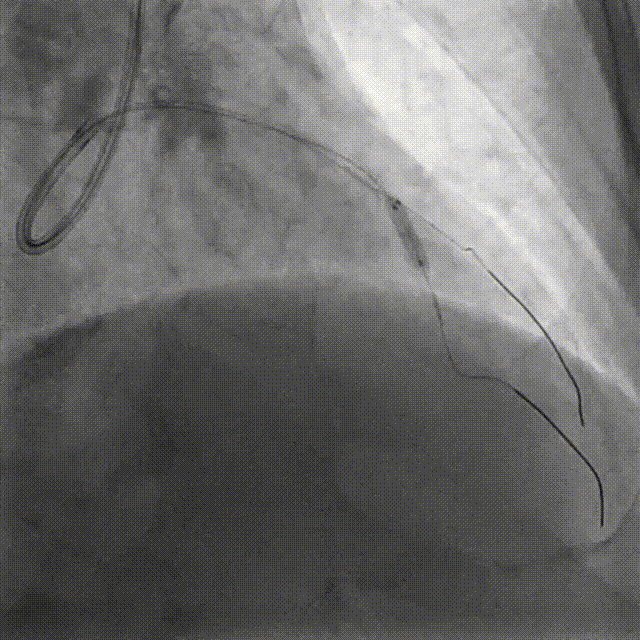

PCI-RCA TR, 7F JR4.0 ROTA with 2.0mm burr

Angiography post-ROTA